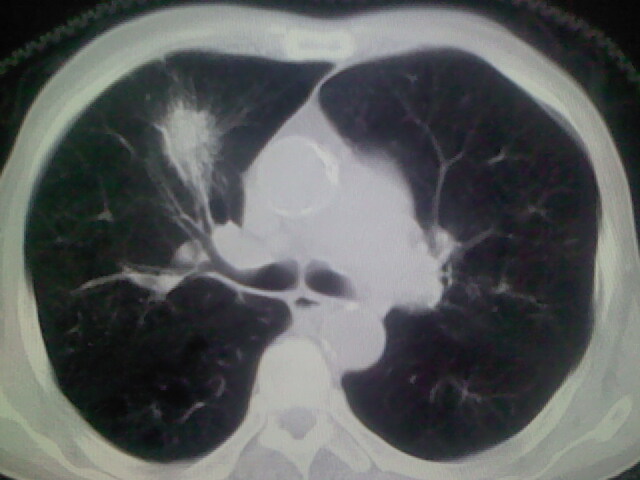

男,70y,胃占位,重度贫血,黑便3月余,伴恶心,纳差,乏力

右上肺周围型肺癌,肝内多发低密度影---转移瘤?建议增强;胃壁明显增厚.

1)考虑右肺上叶周围型肺癌并纵隔及右颈部淋巴结转移,肝脏多发性转移。2)肺气肿。3)冠状动脉及主动脉钙化。

支持右肺上叶周围型肺癌伴肝内多发转移.胃建议充盈后重扫描.慢性支气管炎伴肺气肿.